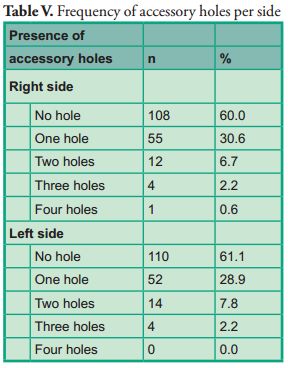

Accessory holes were found in 100 cases (55.5%) out of the 180 tomographies taken (Table V).

Accessory holes were found in 100 cases (55.5%) out of the 180 tomographies taken (Table V).